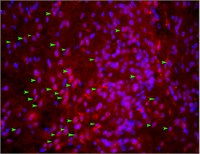

Anti-Mechano Growth Factor (MGF) Antibody is an antibody against Mechano Growth Factor (MGF) for use in Immunohistochemistry (Paraffin), Western Blotting, Immunofluorescence.

| M, H | IH(P), WB, IF | Rb | Affinity Purified | Polyclonal Antibody |